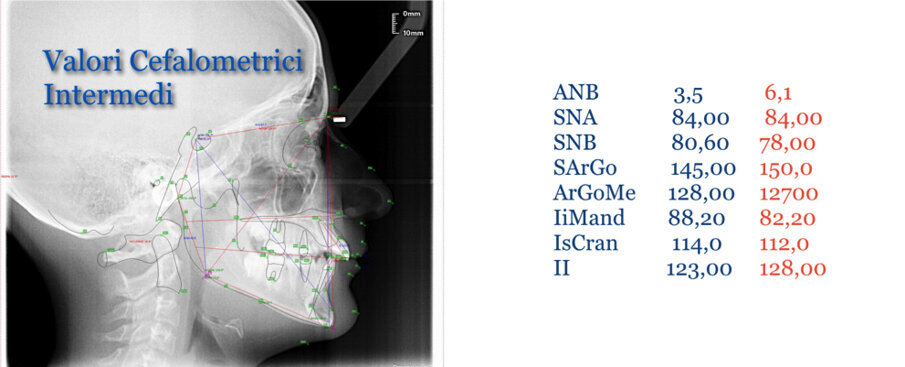

Caso 1 Paziente di anni 9,5, II Classe scheletrica, retrusione mandibolare, contrazione dell’arcata superiore, Overjet elevato (9,5 mm), compressione delle vertebre cervicali. La paziente riferisce di soffrire di cefalee continue. Dall’esame della panoramica e della teleradiografia evince una grande discrepanza tra il condilo dx e sx ed un evidente riduzione dello spazio intervertebrale in corrispondenza delle prime vertebre cervicali. La paziente è sottoposta a terapia elastodontica con AMCOP di seconda classe SC 3 con lo scopo di favorire l’espansione dell’arcata superiore e l’avanzamento mandibolare. A distanza di un anno evince un miglioramento dell’articolazione temporo-mandibolare di sx ed un aumento dello spazio intervertebrale legato a l’avanzamento mandibolare, è evidente inoltre il miglioramento dell’overbite ed overjet. A distanza di 2 anni si assiste ad un netto miglioramento dei condili grazie all’azione scheletrica dell’AMCOP ed a un netto vantaggio posturale con aumento dello spazio tra le vertebre cervicali. La malocclusione si può dire risolta anche se necessita una stabilizzazione del caso clinico attraverso lo stesso dispositivo (Figg. 2-14).

Fig. 2

Fig. 3

Fig. 4

Fig. 5

Fig. 6

Fig. 7

Fig. 8

Fig. 9

Fig. 10

Fig. 11

Fig. 12

Fig. 13

Fig. 14

Il caso clinico dimostra come la malocclusione scheletrica avesse delle forti ripercussioni sulla postura e come risolvendo la malocclusione scheletrica si ha anche un ottimo equilibrio posturale come evince dalle teleradiografie.